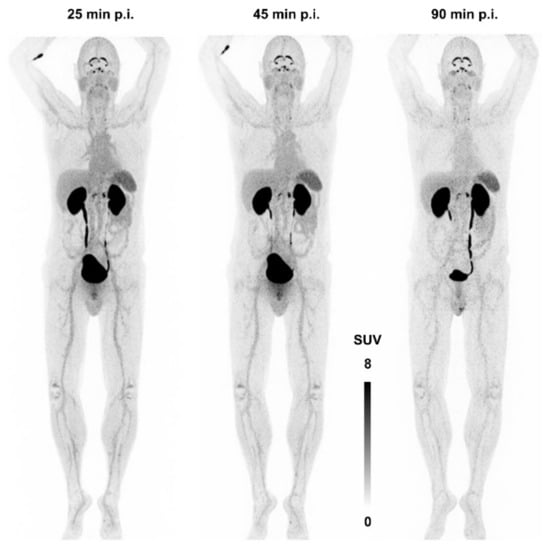

Figure 7 shows the first—and, currently, the only—αvβ8-integrin PET image acquired in human. There is apparently neither a strong specific nor a non-specific uptake in any major organ, apart from a strong signal in kidneys and bladder due to renal excretion. The notion of β8-integrin expression on neural cells (astrocytes) might nonetheless be connected to a substantial uptake in the plexus choroideus and -coeliacus [115]. However, due to a lack of pertinent immunohistochemistry data, no definitive statement can currently be made concerning this observation, and any conclusion would be premature. This situation is quite typical for the entire field of αvβ8-integrin imaging—many hypotheses are not yet supported with enough data and experience. It is nevertheless expected that the knowledge about the in vivo expression patterns of this integrin will substantially grow in the near future, because an imaging tool is now available.

Figure 7.

αvβ8-integrin PET imaging (maximum intensity projection) in human using 68Ga-Triveoctin. Copyright notice: Figure reprinted from EJNMMI Res. 2020, 10, 133. Quigley et al., Tracking a TGF-β activator in vivo: sensitive PET imaging of αvβ8-integrin with the Ga-68-labeled cyclic RGD octapeptide trimer Ga-68-Triveoctin [116]; under Creative Commons CC BY 4.0.